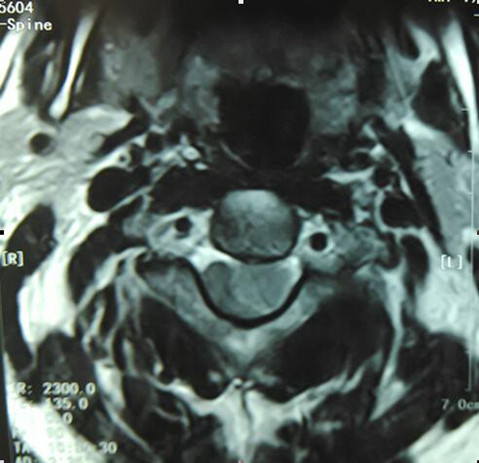

李女士52岁,于入院前一年出现腰部疼痛伴有右侧下肢酸痛,未治疗,入院前一个月,李女士感觉腰部、右侧下肢疼痛加重,休息后不可缓解。心里忐忑的李女士在家人的陪同下来我院就诊。行腰部磁共振检查显示:腰3水平左侧腰大肌轮廓内囊性病灶。入骨外一科后,经谨慎讨论后决定为李女士行T3椎旁肿物切除术。术中顺利切除腰大肌有旁梭形肿物,大小约1×3×2cm3。术后病理回报:(左侧椎旁)良性梭行细胞肿瘤,形态符合神经鞘瘤。术后每一个月至六个月回访,李女士无不适,无复发。

手术难度:该肿瘤在腰3椎体旁、左侧腰大肌内,要将其完整切除有很大难度,极有可能造成左侧腰大肌的损伤及左侧神经根的损伤,导致患者腰部活动受限及左侧肢体运动、感觉障碍,术中必须保护好神经根,若与神经根粘连则不能强行切除。

术前腰椎MRI